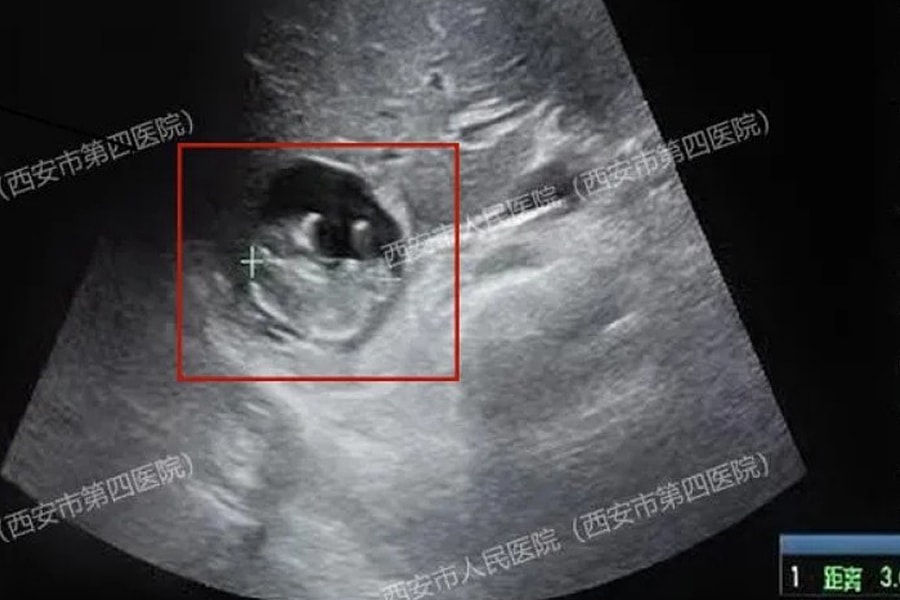

Thai nhi 'làm tổ' trên lá gan người phụ nữ

Các bác sĩ tại Tây An vừa phẫu thuật thành công cho thai phụ 40 tuổi có túi thai phát triển ngay trên bề mặt gan, một tình trạng y khoa cực hiếm.